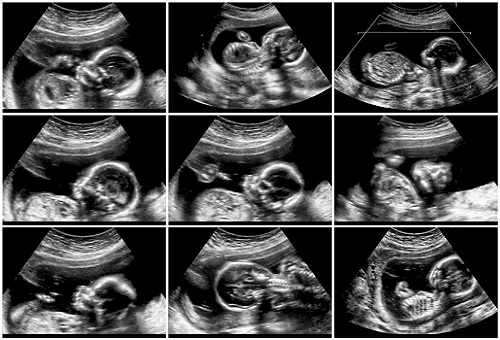

The scan aims to look for any major physical abnormalities in the growing baby. The scan can be as a dating scan where a black and white 2-dimensional (2-D) image is produced which gives the side-view of the baby in the womb. This image shows the baby’s face and hands at 20 weeks and gives the healthcare specialist (a sonographer) an idea of what is going inside. This can be undoubtedly exciting!

Anomaly Scan or mid-pregnancy scan is an ultrasound scan done between the 18th and 21st week of pregnancy to take a closer look at the baby and the womb (uterus) and to have an idea where the placenta is lying.

The mid-pregnancy anomaly scan is done for checking any physical abnormalities in the growing baby. Although it can’t pick up every problem, it gives the healthcare specialist (a sonographer) an idea about the baby’s bones, heart, brain, spinal cord, face, kidneys and abdomen and allows the healthcare specialist identify the following conditions (some of which are very rare):

A sonographer asks the patient to lie on a couch and uncover the abdomen and applies gel on the abdomen. Then he/she passes a handheld probe over the skin of the abdomen to examine the baby’s body. The gel is applied to make sure that there is good contact between the probe and the skin. As the probe moves, a black and white 2-D image of the baby will appear on the ultrasound screen. For a better view, the sonographer will ask the patient to drink water to have a full bladder before the appointment. At times the sonographer may apply slightly more pressure to get a better view of the baby.